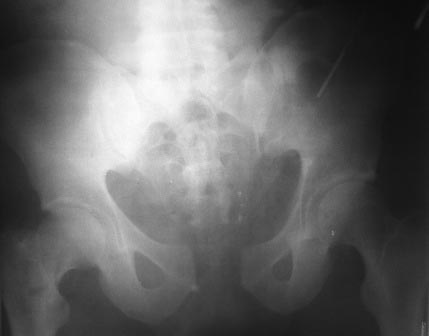

тактике лечения? Снимки: 1. При поступлении. 2. Послеоперационный. 3. от

05.03.2013г.

Имя     : 05.03jpg.jpg

Тип     : image/jpeg

Размер  : 26870 байтов

Описание: отсутствует

Url     : http://weborto.net:8080/pipermail/ortho/attachments/20130306/d918acc1/attachment-0007.jpg